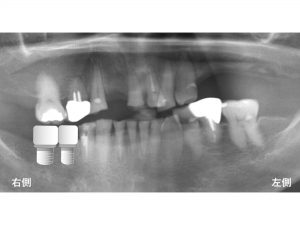

以下は初診時です。

多くの歯が欠損しているので物が噛めないとのことで来院されました。

多くの歯が欠損しています。

以下のバツ印(X)が欠損している部位です。

これらの欠損部位にインプラント治療を行う場合、

以下のようになります。

つまりインプラントは以下の部分のみに行うということです。

以下が治療後です。

最小限のインプラント治療ですが、

患者様は、食事がかなりできるようになり

大変喜ばれていました。